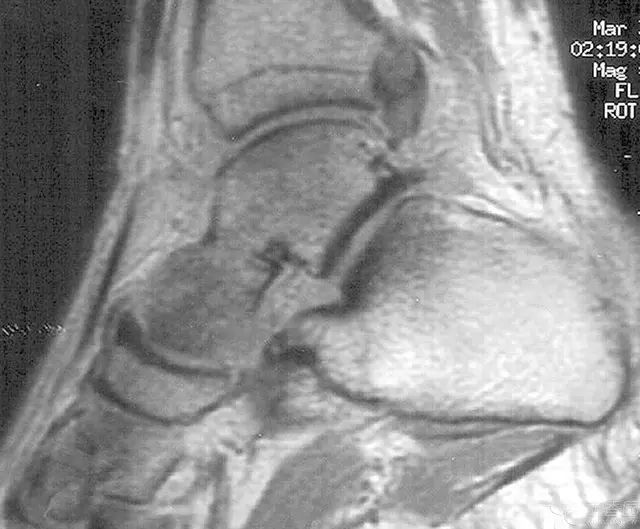

病例三

胫骨远端开放性骨折,远端骨折块游离在体外

游离骨块浸泡在抗生药物生理盐水溶液中

X 线片可见骨块寄养在自体下腹部皮下

创口清创、大量冲洗以后一期外固定支架固定,缺损区域抗生素骨水泥填充

二期回植,更换为钢板内固定

回植后 8 个月,骨折无感染迹象